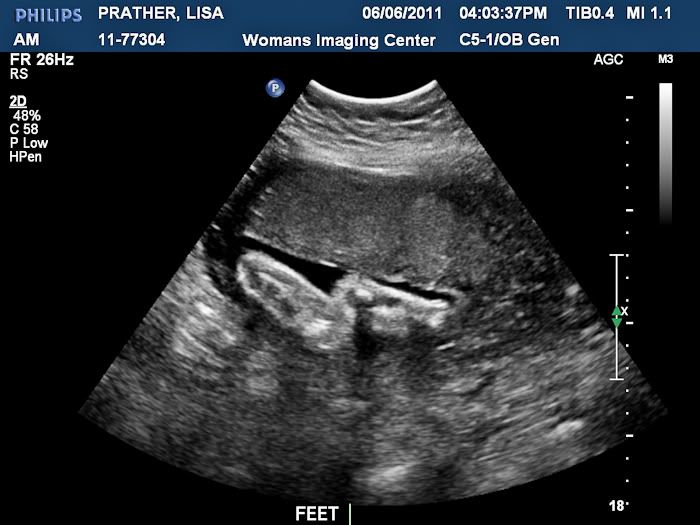

We had an ultrasound today and got to see our baby boy! It was so wonderful to see him, but even better to find out that he is still perfect. He weighs 4 pounds and 11 ounces right now!

Here is his sweet face! I cried when I saw this. I think he is just precious!

Here is a profile shot. You can see one hand up by his face. Both hands were up by his face pretty much the whole time until the end when we decided to stretch his legs by nearly kicking himself in the face!

Cute little feet that like to kick Mommy!

We may have a future gymnast on our hands. His foot is right above his nose!